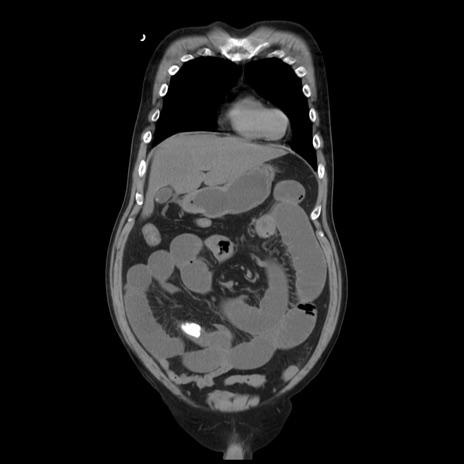

矢状断像

【症例】 60歳代男性

【主訴】 腹部膨満、嘔吐

【現病歴】5日前頃より倦怠感を認め食事量減少し4日前の朝嘔吐、食事摂取困難となった。 3日前近医受診し点滴施行され整腸剤などを処方された。 当日他院を受診し、腹部膨満著明、炎症反応の上昇(CRP10.8、WBC11200)あり、紹介受診となる。

【身体所見】 意識JCS1 受け答えがはっきりしないBP 111/57mHg、 P 67bpm、、BT35.2°C、SpO2 97%(RA)、 腹部:膨隆、打診で鼓音あり、全体的に圧痛有り、腸蠕動音(-)、反跳痛ははっきりせず。

【データ】WBC 11400、CRP 14.20